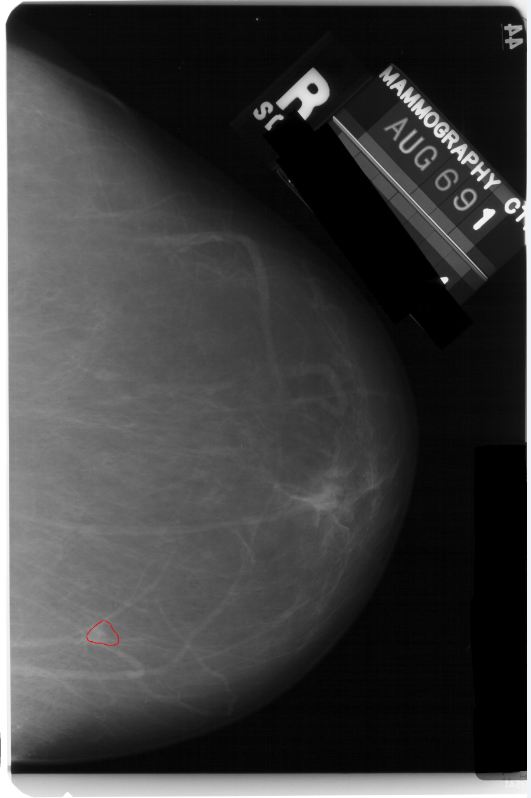

最后把这些点画出来可视化一下看对不对